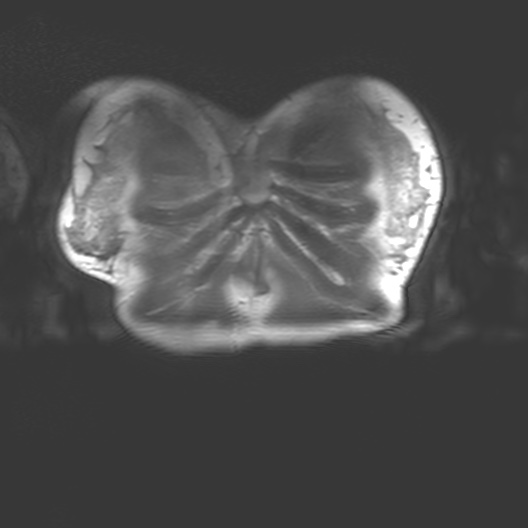

Corporeal matter as perceived by MRI straddles definitions of substance, organism, subject and object. MRI interacts with the body through nuclear magnetic resonance and electrodynamics, bringing us into contact with the body as a person, as an assemblage of biochemical reactions, as a patient and a cellular, molecular, atomic and subatomically composed entity.

MRI is a non-invasive biomedical imaging technology that visualises tissues within the body. MRI is an interesting piece of physics that interacts with the body. As a technology it draws on the quantume mechanical properties embedded in corporeal matter - particularly hydrogen ions, also known as protons (H+). MRI brings together multiple aspects of our ontology. MRI interacts with the body through nuclear magnetic resonance and classical electrodynamics and thus physics allows us to connect to the abject. This brings us into contact with the body as a person, a patient, a member of a community, and as a cellular, molecular, atomic and subatomically composed entity.

I began my investigation by taking part in MRI trials at the Cancer Centre in 2018 with Dr Heather Fitzke. MRI images confront us with the fact that our bodily materiality acts beyond us and that medical technology shapes our sense of self.

Seeing my organs autonomously pulsing on the monitor in the control room had a pronounced impact on me. It was like looking into a rockpool within my own body. The affecting power of MRI (its power to change our emotions) is in its potential to reveal autonomic bodily functions and diseases which are beyond our control. The data on the screen revealed my autonomous self: peristalsis, bowel movements, digestion, heartbeats and respiration. Through MRI, anatomy is seen as embedded and relational.

I felt a deep sense of fascination with how my organs moved and worked. Haraway’s situated biopolitics argues for an account of the body as an environment, in a state of simultaneous dissolution and formation which I notice in my data. My organs seemed like invertebrates in a rockpool: a squishy pulsing ecosystem. Organs do not operate in isolation but are interconnected. Their autonomous pulsing and motion seemed creaturely and strange in contrast to my numerous encounters with preserved cadavers in the dissecting room. My organs keep me alive yet I have no conscious sense of their functioning. They function beyond me.